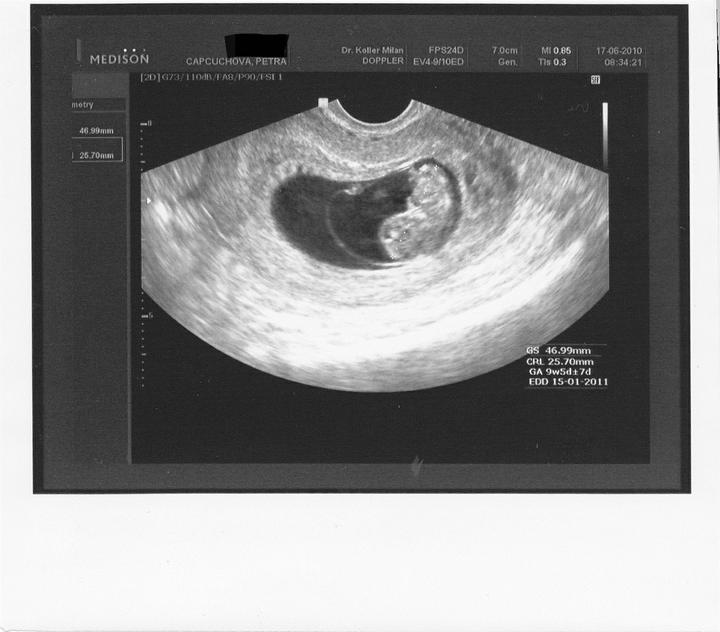

13.5. jsem byla na odběrech hcg, jehož hodnota byla 994, hodnota byla dost vysoka na 13. den.